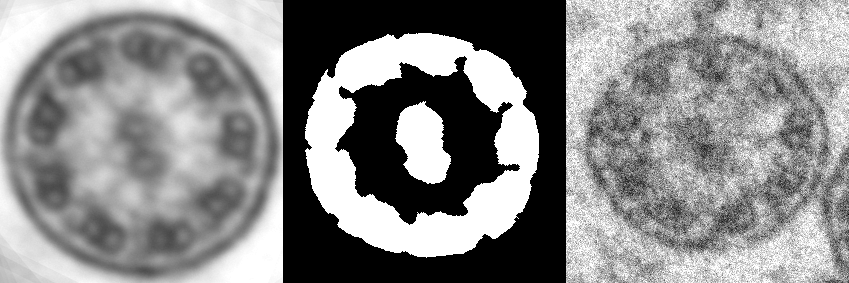

Figure 1. Content of dataset: synthetic noise-free cilia reference, feature mask, and real short-exposure cilia image